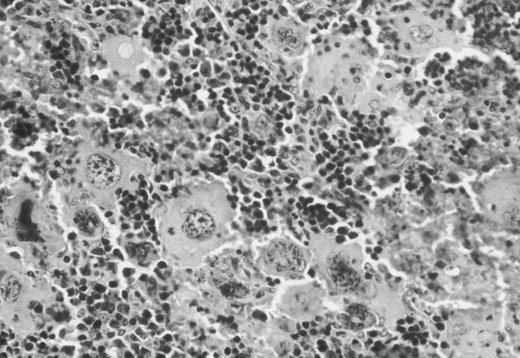

Binding of 125I-Tpo to NF-E2−/− megakaryocytes and megakaryocyte fragments in vivo.Although blood platelets, which carry approximately 200 c-Mpl molecules per cell in mice,10 are likely to be the major source of this receptor, it is also expressed on megakaryocytes. Loss of NF-E2 in vivo is accompanied by megakaryocytosis,14 marrow hypercellularity, and splenomegaly.20 Indeed, prior studies may have underestimated the degree of megakaryocyte hyperplasia in the steady state; extensive review of spleen and bone marrow histologic sections reveals considerable expansion of the megakaryocyte population in adult mice (Fig 4). Thus, a substantial amount of c-Mpl may be available on NF-E2−/− megakaryocytes to sequester free Tpo from the circulation.

Hematoxylin-eosin–stained representative histologic section of the spleen of a 12-week-old NF-E2-null male mouse showing the dramatic increase in the number of megakaryocytes.